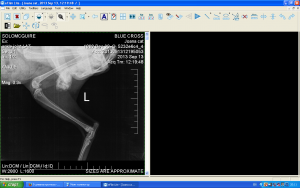

За съжаление новините от Йоана не са добри.Няколко месеца след осиновяването и се появи проблем с крачетата.Наложи се да се направи операция на пателата(разместени капачета на коленете),много рядка диагноза за котка,но "нашата" Йоана твърдо е решила да не е обикновенна котка.

Но дори и след операциите на крачетата,Йоана някакси има странна стойка.Не се отразява на подвижността и,не дава признаци да има болка или дискомфорт,но задните и крачета са някакси в неестествена позиция.

Заведохме я за снимка в Син кръст,казаха че операцията е направена добре и няма нужда от друга.